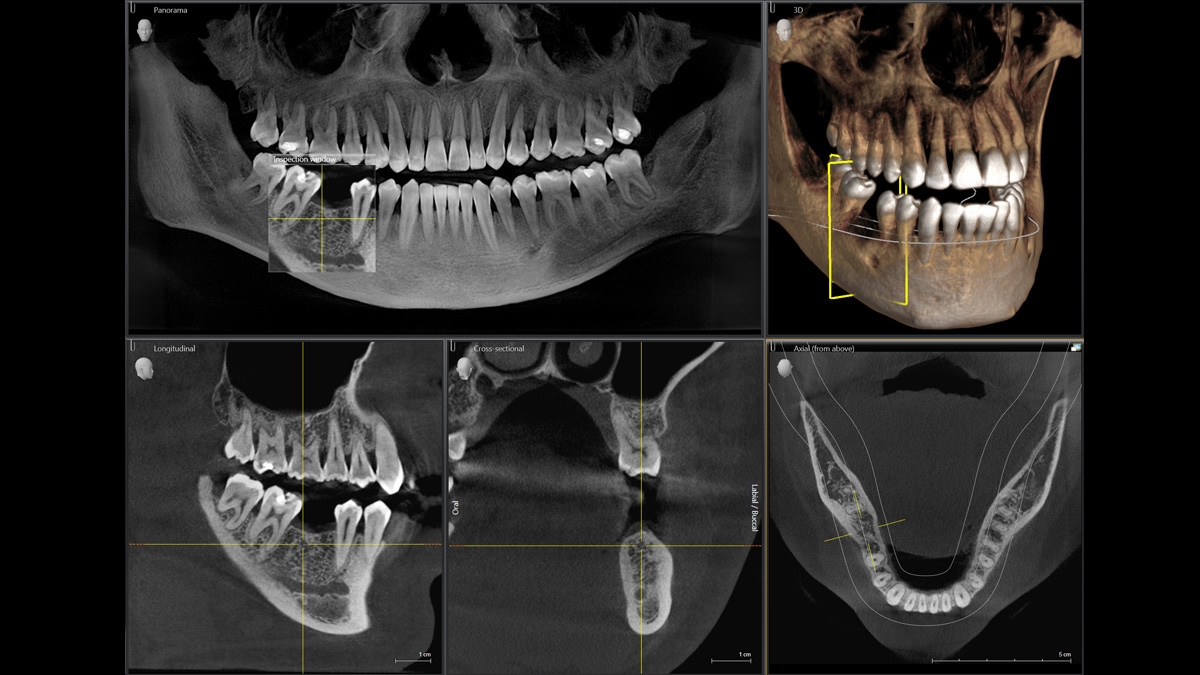

Диагностика последнего поколения, идеально решающая задачи рентгеновского обследования независимо от размеров клиники. Поля изображения зависят от определенной клинической картины, поэтому специалистам так удобно работать с ORTHOPHOS SL 3D. Данная установка делает объёмные картинки для одиночной реставрации в 3D качестве полностью всей челюсти такого размера, которого требуется.

ОБЪЁМ ДЛЯ ЛЮБЫХ ЦЕЛЕЙ

Планирование одиночной реставрации, эндодонтические исследования и пр. – для этого специалист может выбрать объёмные варианты 8 х 8 см или 11 х 10 см, также предлагается объём 5 х 5,5 см. Снимки в HD-качестве, стандартные настройки или выбор объёма обследования в зависимости от диагноза — всё это врач получает в отличном качестве, а для пациента излучение в районе исследования минимально.

Конструктивные особенности датчика DCS заключаются в превращении рентгеновского излучения в электрическую энергию. Обычная для таких случаев промежуточная стадия светового луча отсутствует. Другими словами, значительно снизив потери сигнала, производитель максимально улучшил чёткость.

С технологией SL можно за один сеанс получить огромное количество снимков. Те из них, где фокусировка наиболее чёткая, автоматически соединяются. В итоге одна процедура — снимки челюсти полностью в самом лучшем качестве. Даже нестандартные случаи не станут помехой в обследовании. К примеру, при ретинированных зубах уже после того, как снимок сделан, нужную область можно выделить подробнее, и в ещё одном рентгене необходимость отпадает.